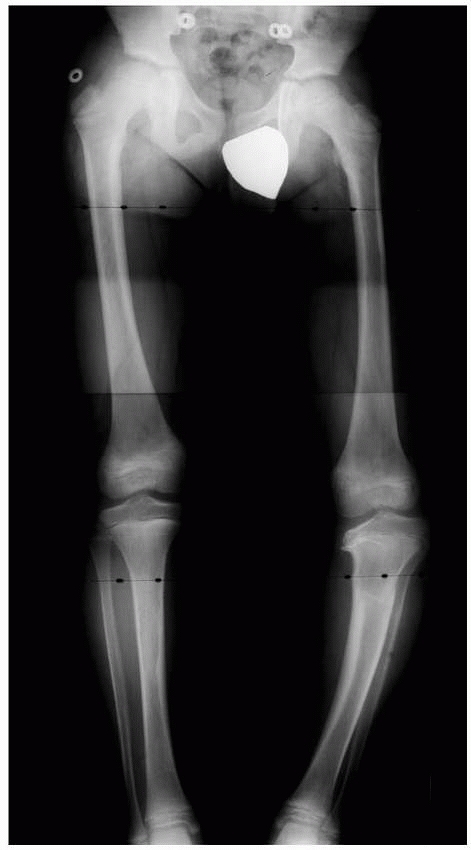

| Figure 5-6 Standing anteroposterior lower extremity radiograph of a 12-year-old boy with multifocal physeal disturbance from purpura fulminans associated with meningococcemia. Radiograph abnormalities are present in the left proximal femur; both distal femoral epiphyses, including partial arrest of the left distal femoral physis; and both distal tibial epiphyses. The patient also has digital amputations and extensive soft-tissue scarring resulting from this septic event. |

| Figure 5-36 Physeal arrests create variable amounts of limb shortening, angular deformity, and epiphyseal distortion, depending on the duration of the arrest, the physis affected, and the size of the arrest. A long, standing film of the lower extremities with the hip, knee, and ankle joints included provides an overall assessment of angular deformity and shortening. |